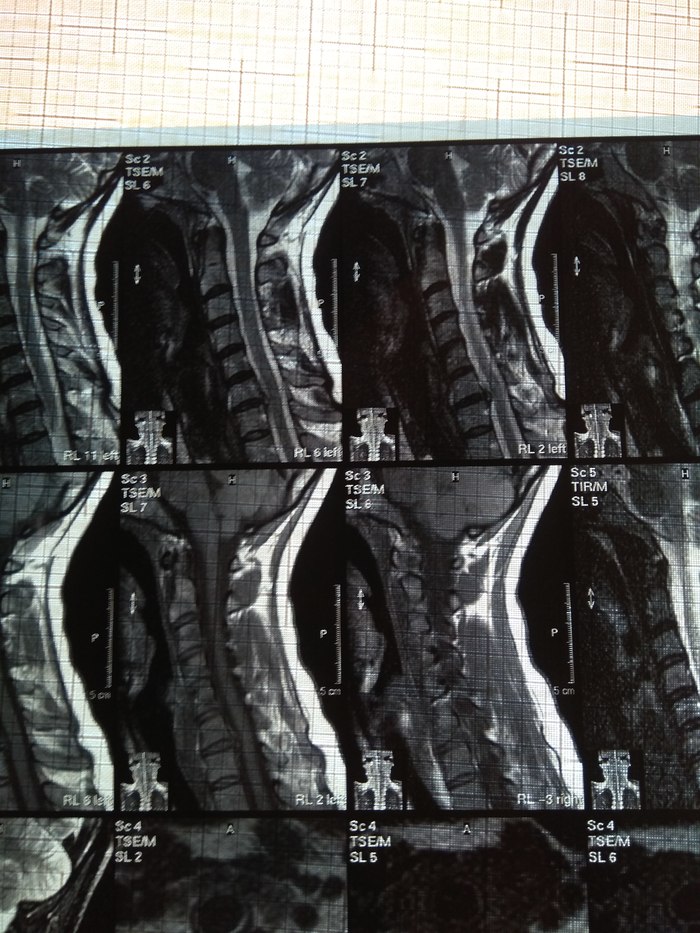

У подруги случилась проблема, тянула с визитом к врачу и в итоге потеряла сознание, вызывали скорую и направили к неврологу. Онемение пальцев на правой руке, сильные боли до судорог и потери сознания. В итоге невролог направил на МРТ и к нейрохирургу, выписали ношение ортопедического воротника, 2 вида уколов и таблетки, названия навскидку не помню. Сказали если через 10 дней не полегчает, то на операцию. Сегодня 5й день, никаких улучшений, рука с каждым днем выше немеет, но подвижность пока в норме. В день по 2-3 раза колет кетонал. Я вот переживаю как бы рука не отказала. Такое может случиться?